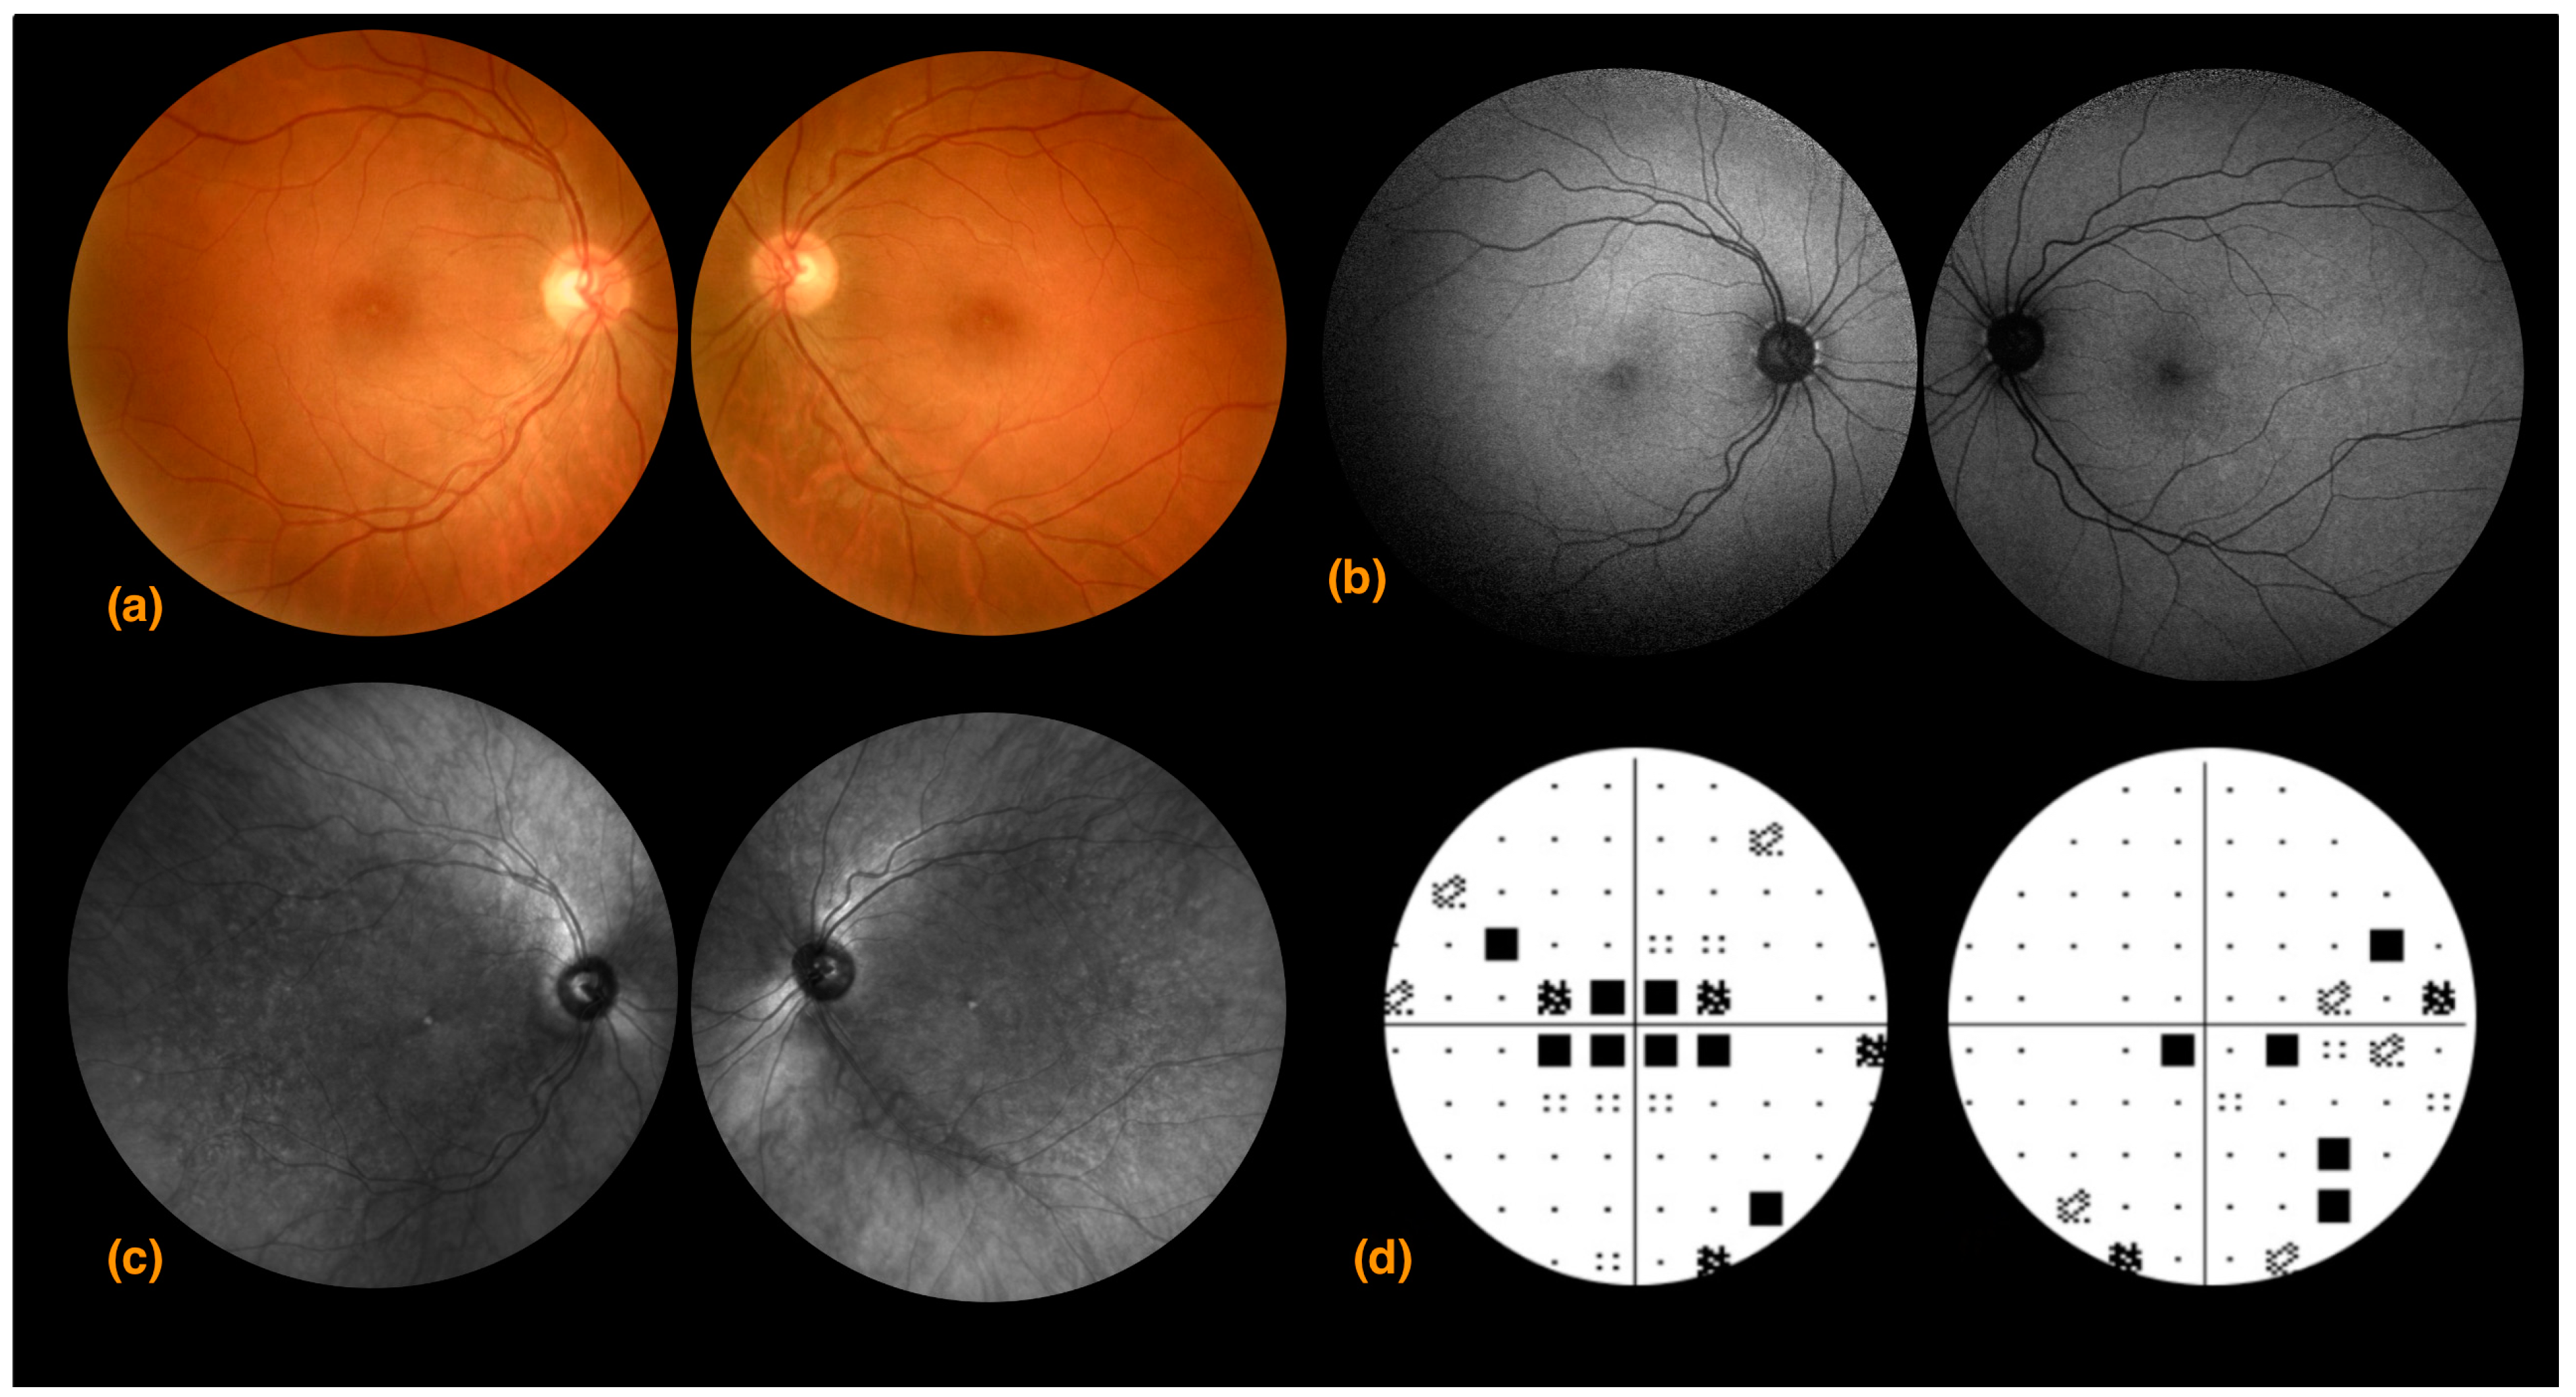

3.3. Case 3